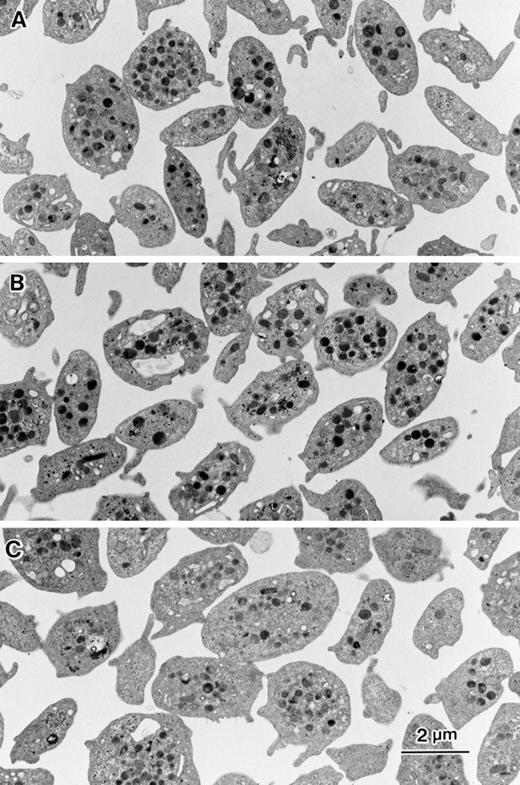

Ultrastructural analysis was performed to evaluate the effects of inhibitors on platelet shape, aggregation, and granule release. Unstimulated platelets showed discoid shape with small and short pseudopodia (Fig 7A). In the presence of 10 μmol/L DCB the platelets maintained discoid shape similar to control platelets (Fig 7B). However, platelets incubated with 80 μmol/L bepridil tended to be round shaped (Fig 7C). Fifteen-minute incubation of thrombin-stimulated platelets in the presence of 0.1% DMSO resulted in the formation of small aggregates (10 to 20 platelets). Each platelet showed pseudopodia formation and granule secretion (Fig 8A). In the presence of 10 μmol/L DCB, both pseudopodia formation and granule secretion were induced by thrombin, whereas the formation of platelet aggregates were markedly reduced (Fig 8B). Bepridil, similar to DCB, strongly inhibited aggregate formation by thrombin (Fig 8C). Although the pseudopodia formation was impaired, the stimulated platelets had no granules in the cytoplasm, suggesting that the release reaction had occurred even in the presence of bepridil (Fig 8C). These ultrastructural analyses confirmed the inhibitory effects of NCX inhibitors on platelet aggregation and also showed that granule secretion induced by thrombin occurred in the presence of NCX inhibitors. Thus, NCX inhibitors, particularly DCB, seemed to make platelets thrombasthenic.

Effects of DCB or bepridil on morphological changes in intact platelets. Washed platelets (5 × 105/μL) were suspended in modified Tyrode Hepes buffer containing 1 mmol/L CaCl2 and mixed with 0.1 % DMSO (A), 10 μmol/L DCB (B), or 80 μmol/L bepridil. After 15 minutes of incubation, equal volume of 4 % glutaraldehyde containing phosphate buffer was added to each aliquot. Electron microscopic analysis was performed as described in Materials and Methods.

Effects of DCB or bepridil on morphological changes evoked by thrombin. Washed platelets shown in Fig 7 were stimulated by 0.1 U/mL thrombin under unstirring condition. After 15 minutes of incubation, equal volume of 4% glutaraldehyde containing phosphate buffer was added to each aliquot. Electron microscopic analysis was performed as described in Materials and Methods.